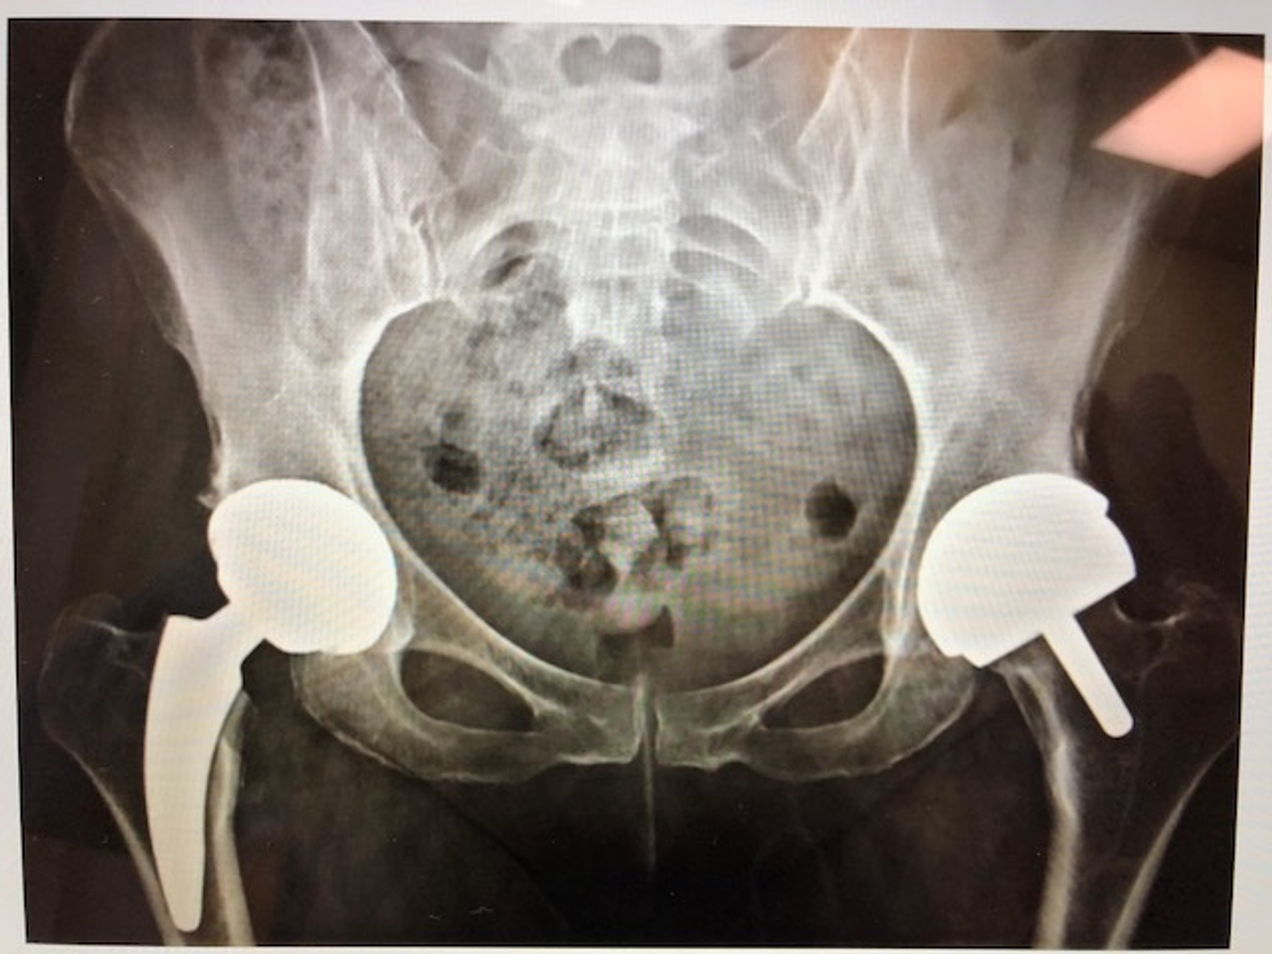

• Реабилитация после эндопротезирования

• Эндопротезирование суставов (артропластика)